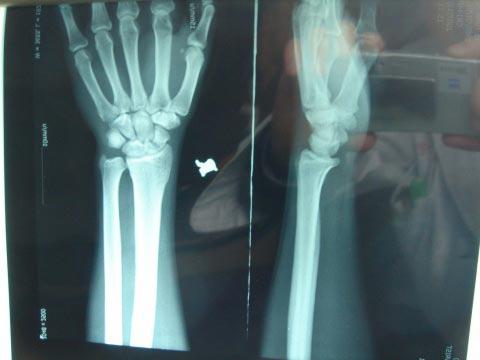

(图:经医托事件后,患者因为失去最佳治疗时期引起关节变形)

来院后,杜爱华主任便开始为赵女士进行一系列全面的检查,4年的误药经历,让赵女士的双手关节肿胀严重,甚至出现变形,手部不仅不可以握拳,伸直也不能,情况比较严重,需要立即开展治疗。在了解了赵女士的病情以及自身状况后,杜爱华主任为她制定了详细的 方案。